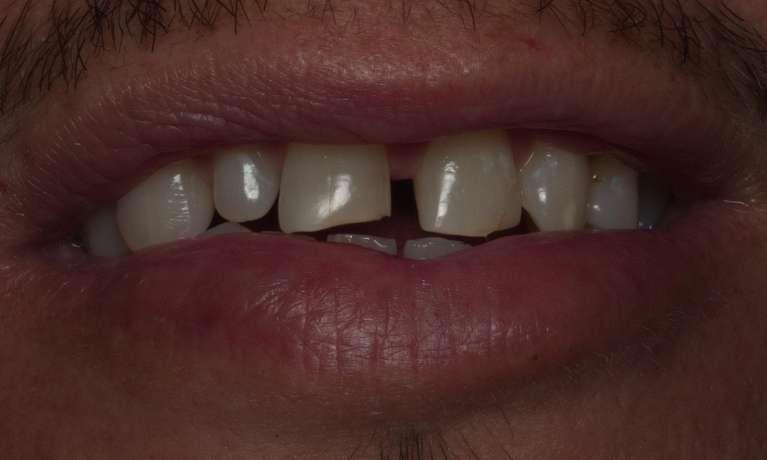

At Springs Family Dental, we know that sometimes cavities happen, and we want you to know that we are here for you and your family. With natural-looking fillings that blend beautifully with your own enamel, we can restore your tooth and its functionality – and nobody will ever know that you’ve had a cavity.

Even with diligent brushing and flossing alongside dental check-ups, cavities can still happen. In the past, the only options for fillings were porcelain, gold, or silver amalgam materials. The problem with metal amalgams is their tendency to darken over time, as well as requiring removal of healthy tooth structure to hold the filling.

With advancements in dental technology and materials, our Colorado Springs dental office can now offer tooth-colored composite resin fillings. Not only do tooth-colored fillings blend in seamlessly with your smile, but they also require less removal of your tooth structure to bond with your tooth.

Tooth-Colored Composite Fillings

Our office provides a variety of different filling materials to suit the individual needs of each patient; however, most of these fillings are tooth-colored composite. Composite has many benefits, such as blending naturally with the tooth, bonding to the remaining structure, and acting relatively inert in your mouth.